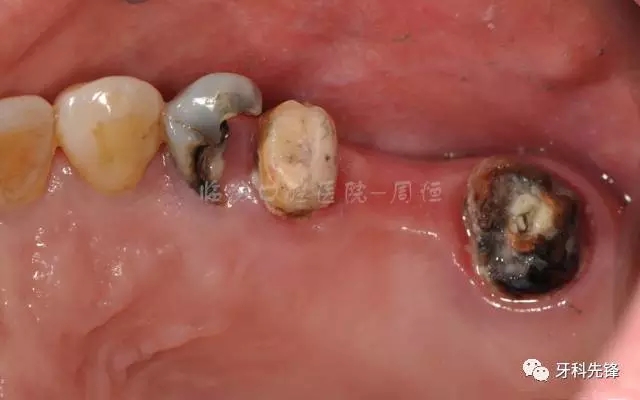

患者:郭某某女55歲

主訴:右上后牙修復體崩瓷,松動兩個月左右

現(xiàn) 病 史:患者兩個月前右上后牙修復體邊緣不密合,松動崩瓷,近期不適加重要求重新修復,來診

檢查:15 16 17 烤瓷冠修復體,崩瓷,邊緣不密合,食物嵌塞,齦下牙石II°,冷熱診無不適,叩診(+),牙齦輕微紅腫。

14  殘冠,位于齦下2mm,牙齦顏色正常,叩診(-)

46  頜面充填體近中有懸突,PD:10mm,根分歧III°,陰影較大,叩診(+),牙齦輕微紅腫。

圖2  術前側位咬頜照

圖3 術前頜面照